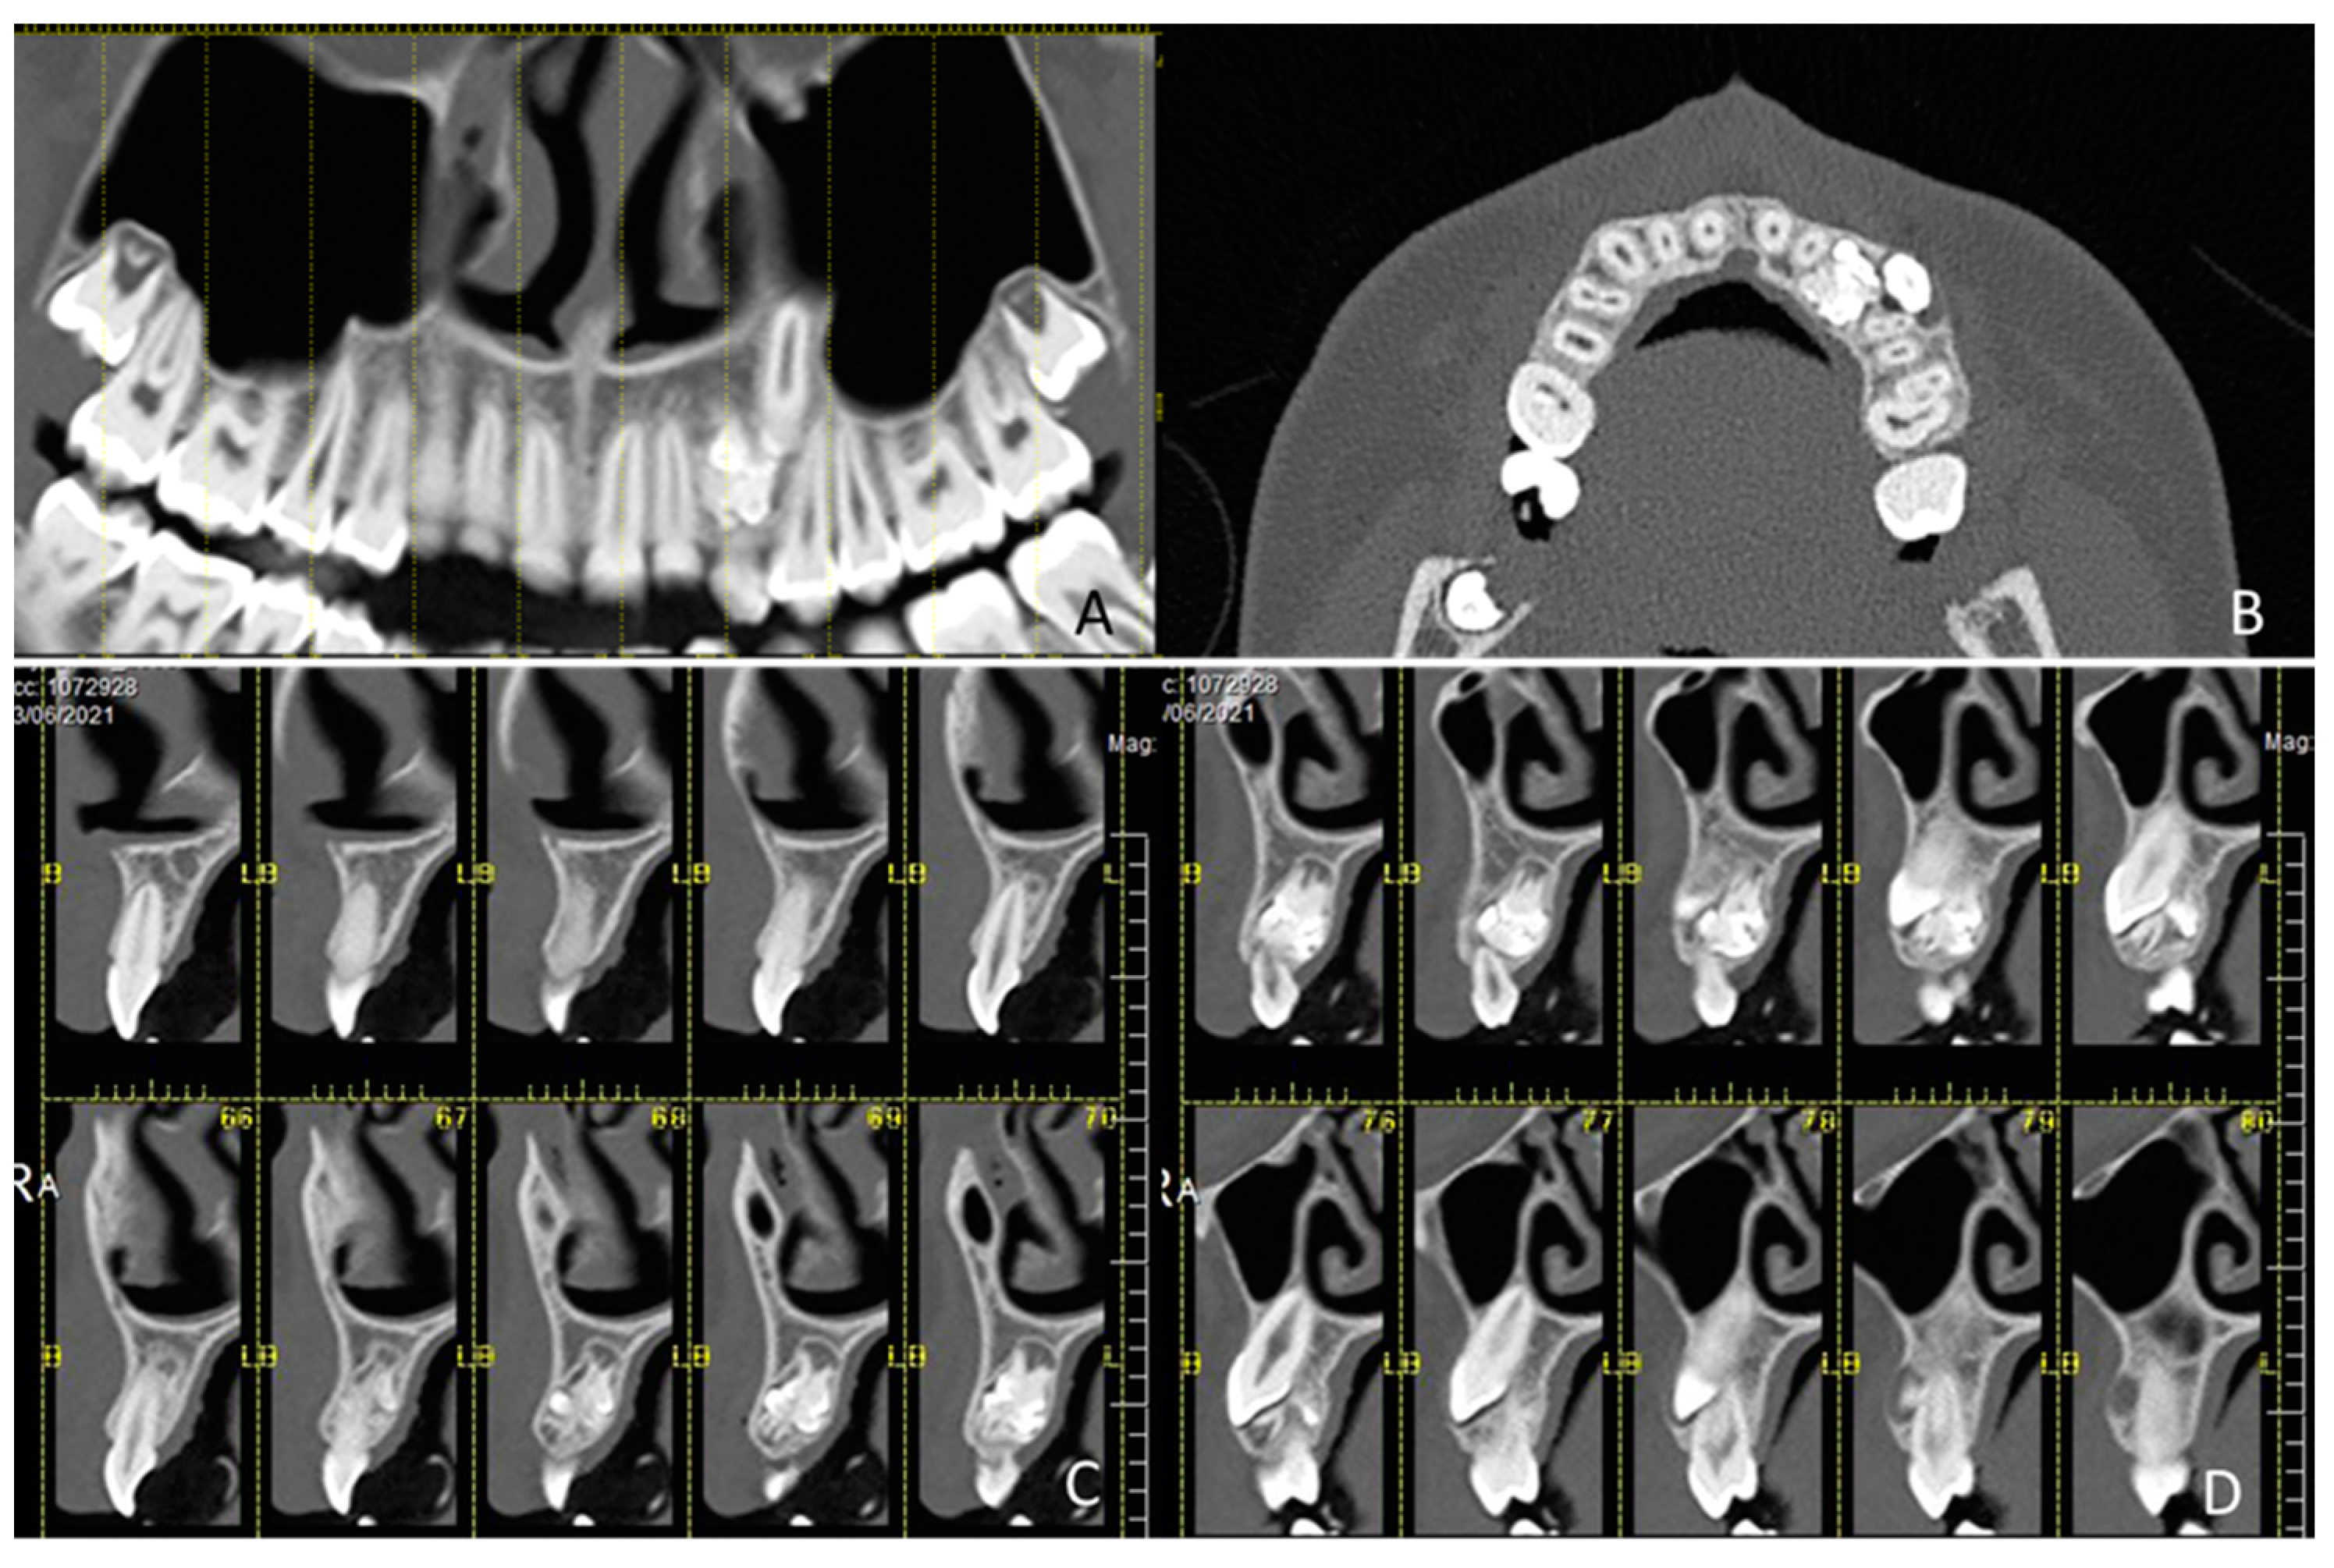

1.1. Case Number 1